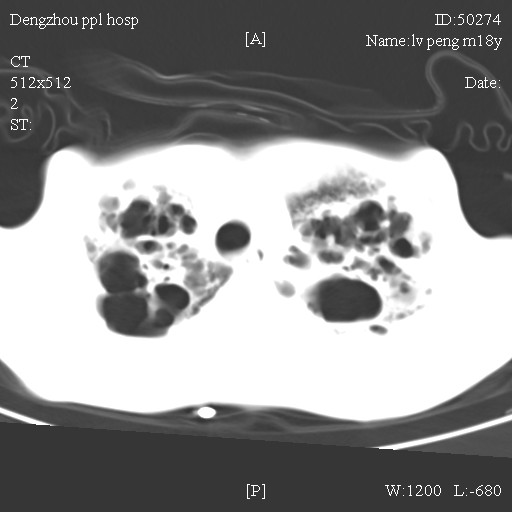

标题: CT10510:男.18岁,咳嗽咳痰两月.(有病理) [打印本页]

标题: CT10510:男.18岁,咳嗽咳痰两月.(有病理)

双肺布满大片状实变及网格状结节影,内参杂大小不等的气囊及空气支气管征,心脏增大。考虑:1 全身结缔组织疾病—系统性红斑狼仓?2 肺泡蛋白沉积症合并感染!

双肺布满大片状实变及网格状结节影,内参杂大小不等的气囊及空气支气管征,双侧胸膜腔少量积液,双下肺近膈面透亮度尚可,病人较年轻,病变较重(不知为什么上胃管?)考虑:1.胶原病肺部改变,2.组织细胞病x。结合实验室检查。

首先考虑组织细胞x病。两肺中上肺野多发囊腔,中下肺野内见多发小结节,并可见肺间质增厚。患者是男性,年龄较小。胶原性病变比较多见的类风湿、系统性红斑狼疮和硬皮病临床和影像均不是很支持,类风湿和系统性红斑狼疮的肺部表现最常见的是胸腔积液,硬皮病可见食管的扩张。

肺内多发斑片状、结节状、融合大片状及网格状影,多发薄壁空腔影,胸膜肥厚,纵隔、气管右移,考虑ⅲ型肺结核,多发空洞,继发肺间质纤维化。

双肺结核并播散.患者以肠梗阻入院,手术为肠结核.术后咳嗽做ct检查.